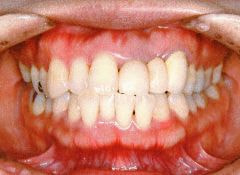

治療例1 (インプラント補綴+矯正)